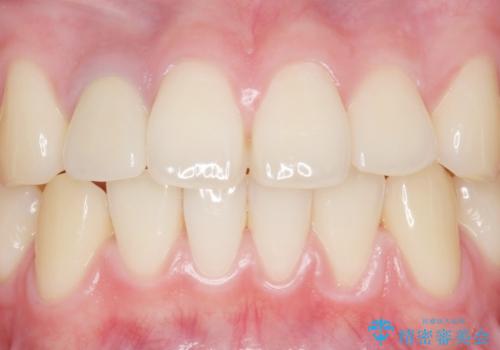

土台を白いファイバーコアにやりかえたのち、土台の色を透過させないジルコニアフレームを用いたセラミッククラウンによる治療を行いました。

自然な仕上がりにご満足頂けました。

治療終了時には「修正や仮付けをしてもらえて納得のいく治療を受けられました。この病院にして良かったです!」とおっしゃって下さいました。

クラウンの種類:オールセラミッククラウン スペシャル